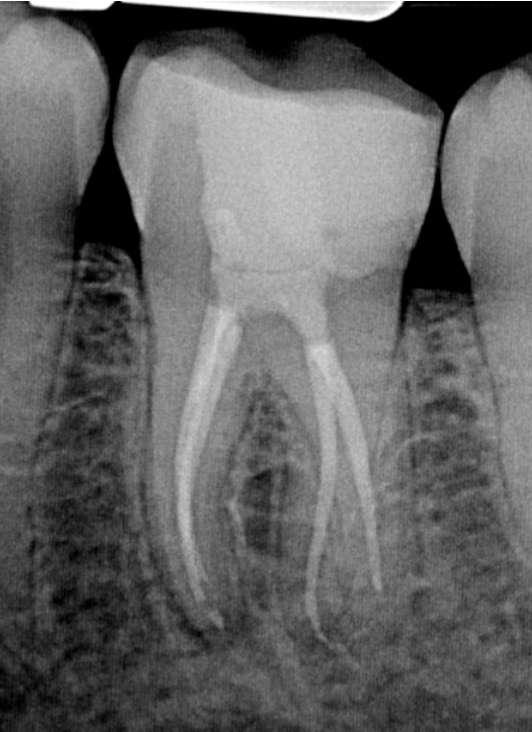

Das Röntgenbild zeigte eine große Länge und einen gemeinsamen Ausgang für zwei der drei mesialen Kanäle.

Die Wurzelfüllung erfolgte mit einer einzigen Kegeltechnik unter Verwendung des BUSA EndoSequence Bioceramic Sealer. Das Post-OP-Röntgen zeigt sehr hohe Dichte in der gesamten Länge der Wurzelfüllung.